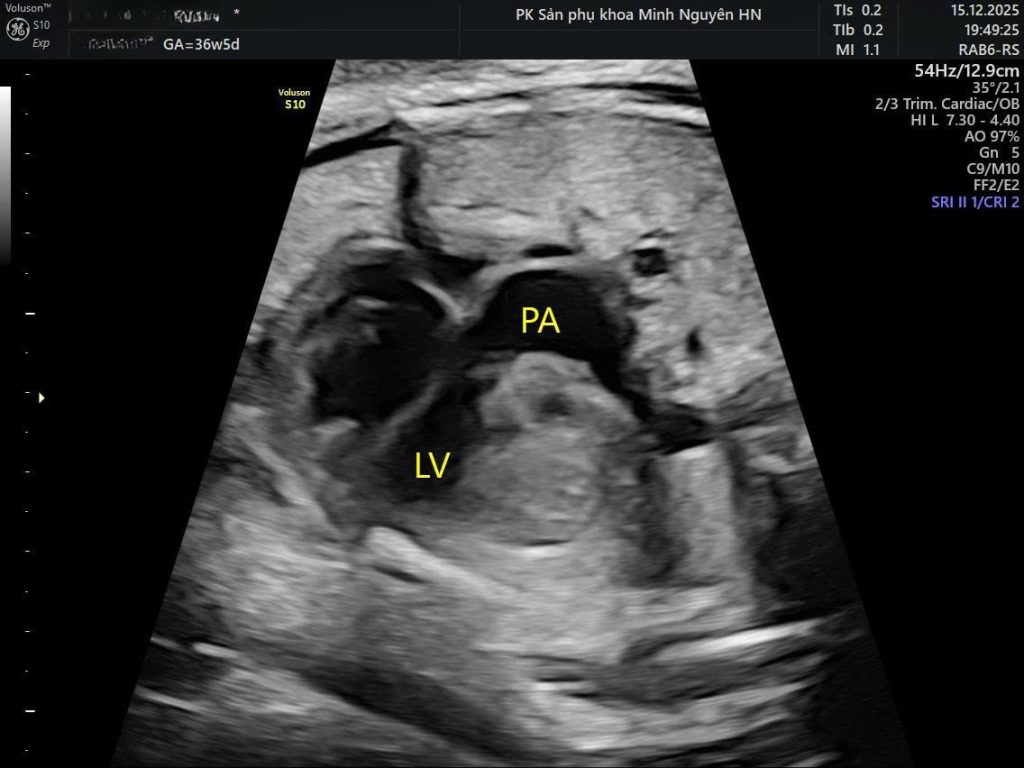

Dấu hiệu quyết định nằm ở:

- Mặt cắt đường ra hai thất

- Mặt cắt ba mạch máu và khí quản

Bình thường sẽ thấy hai đại động mạch bắt chéo nhau (dấu hiệu X).

Trong đảo gốc động mạch sẽ thấy hai mạch chạy song song (dấu hiệu I).